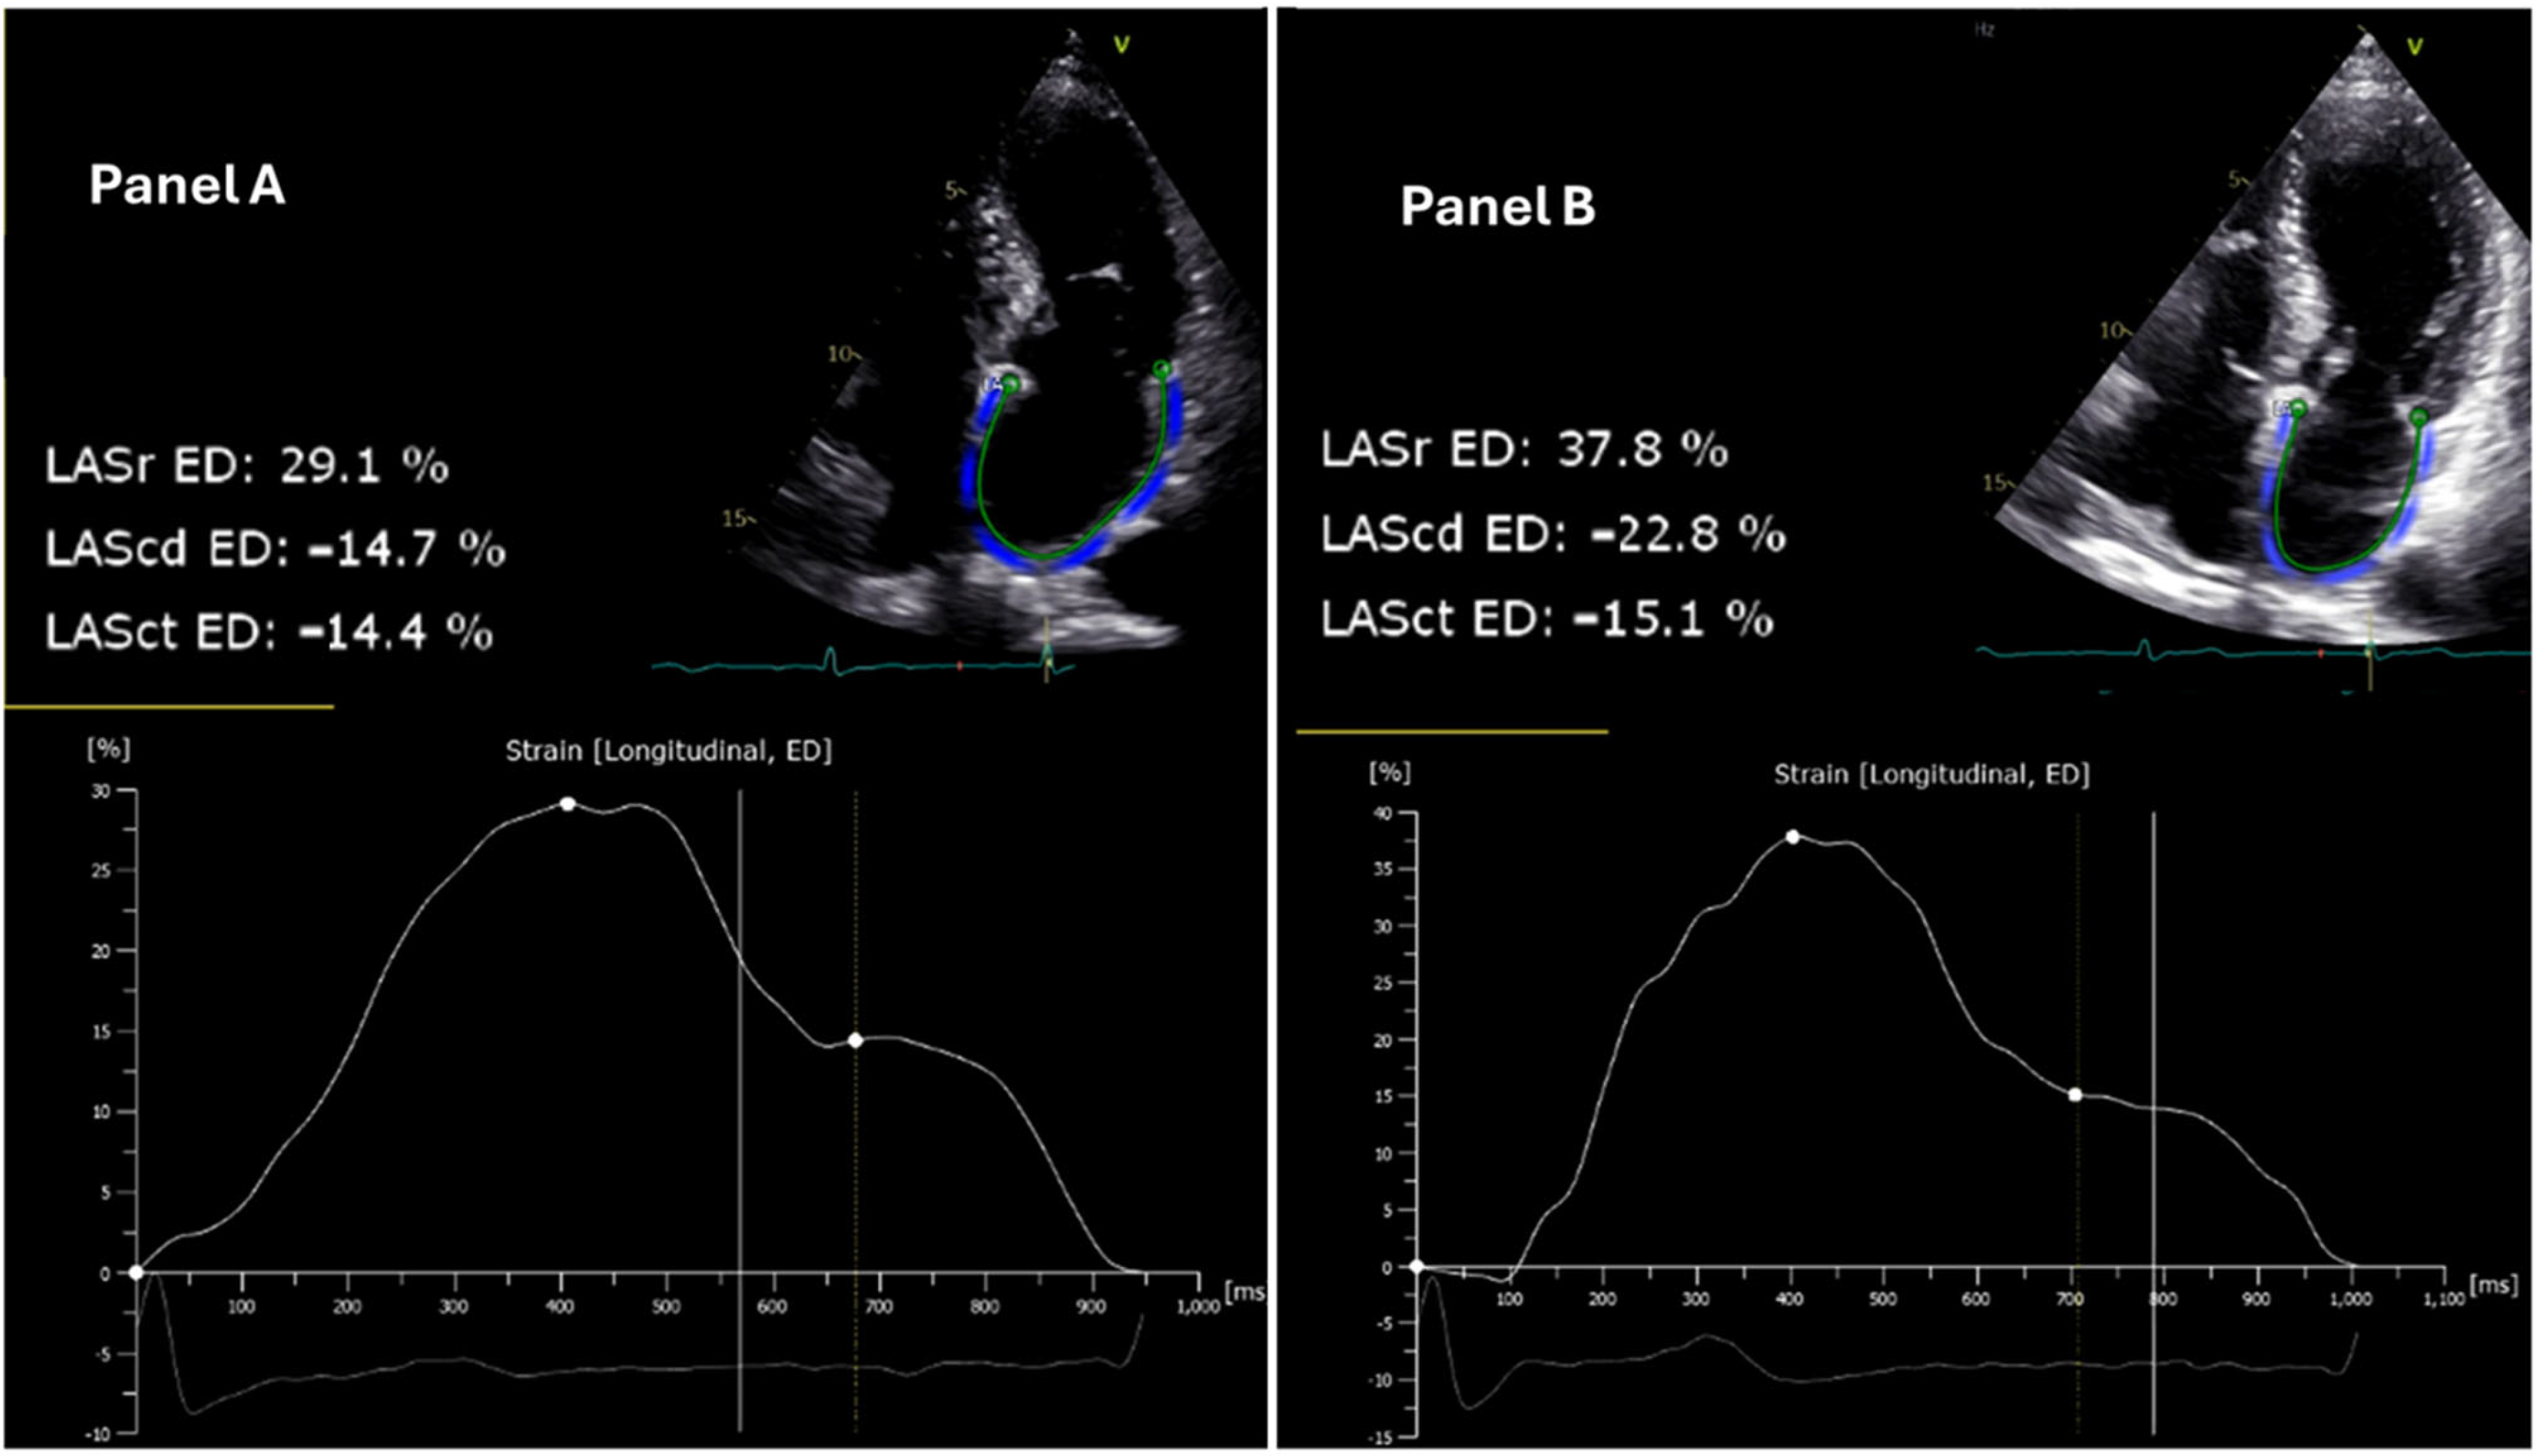

Pre- and post-interventional echocardiographic assessments were performed using a standard protocol. Left atrial (LA) strain measurements were conducted using Tomtec software Version (LOT): 41.00 and quantified by two-dimensional speckle-tracking echocardiography with TOMTEC-ARENA post-processing software (Tomtec Imaging Systems GmbH, Unterschleißheim, Germany) (Figure 1). LASr, LAScd, and LASct were assessed using 2D speckle-tracking echocardiography (STE). This technique tracks the motion of myocardial speckles in a frame-by-frame manner, allowing for the assessment of myocardial deformation (strain).

Figure 1. Echocardiographic assessment of left atrial strain reserve in patient 14 before and after pulsed field ablation. The left atrial reservoir strain (LASr), conduit strain (LAScd), and contractile strain (LASct) at the end diastole (ED) are illustrated. (Panel A) (left): Pre-ablation two-dimensional speckle-tracking echocardiogram demonstrating a LASr of 29.1%. (Panel B) (right): Post-ablation two-dimensional speckle-tracking echocardiogram depicting an increased LASr of 37.8% in the same patient, indicating an improvement in LASr function following the intervention. The strain curves below each echocardiogram reflect the changes in deformation of the left atrial wall over the cardiac cycle, with significant augmentation observed post-ablation.